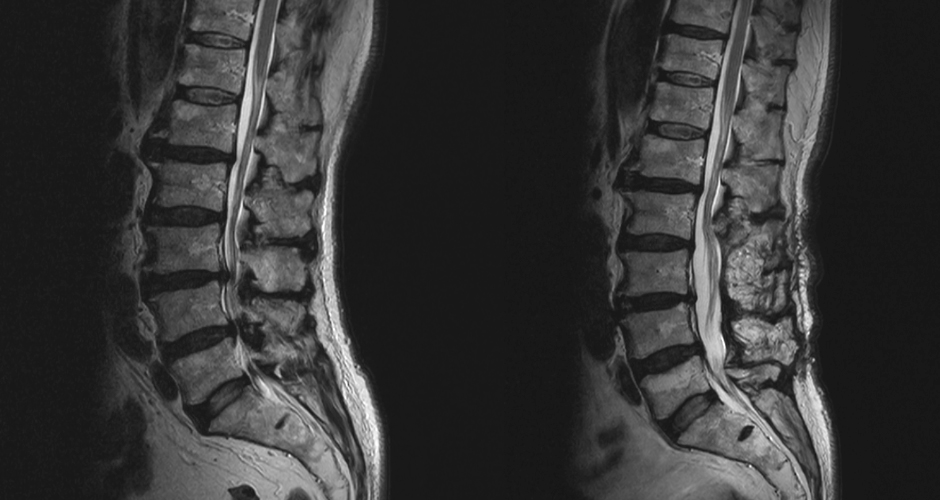

腰部脊柱管狭窄症

腰部脊柱管狭窄症に対する椎弓切除術(左:術前、右:術後)